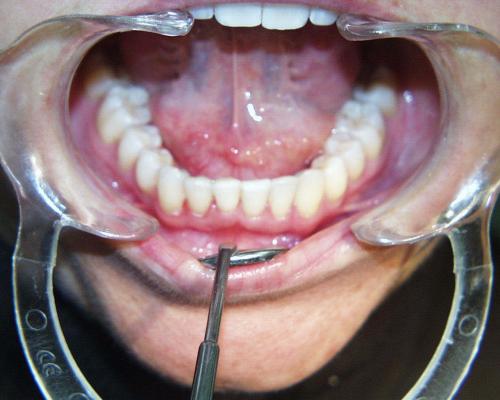

Nach der Behandlung

(Dauer der aktiven Behandlung: Im Oberkiefer 7 Monate, im Unterkiefer 1 Jahr, 4 Monate)

Sehr gute Stabilität nach 12 Jahren